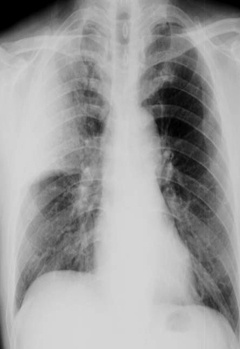

圖中可見右上葉“一片白”,根據公式診斷為右上葉大葉性肺炎